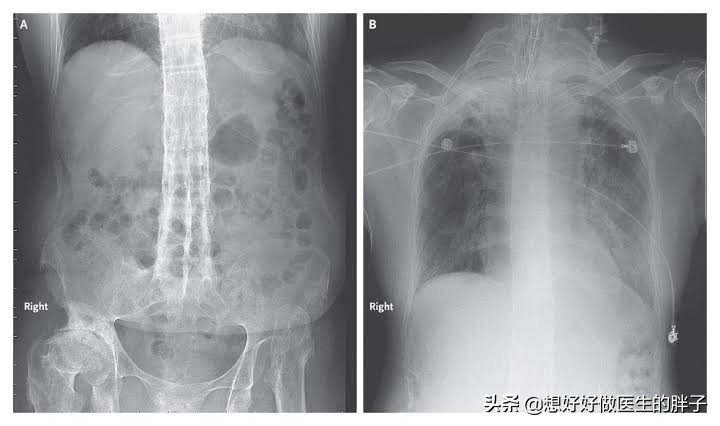

得了强直性脊柱炎确实是非常让人痛苦的一种疾病,因为慢慢的脊柱的功能以及关节的功能会出现明显的障碍和疼痛,很多患者难以抵抗这种病理性的改变,情绪发生了很大的变化。但是这种疾病是对生命进程影响不是很大的,虽然有一些并发症,但是确实有大量患者病情得到了明显的控制,没有进一步的影响生命,下图这位外国报道的患者与强直性脊柱炎共存36年,并没有影响他的生命进程。